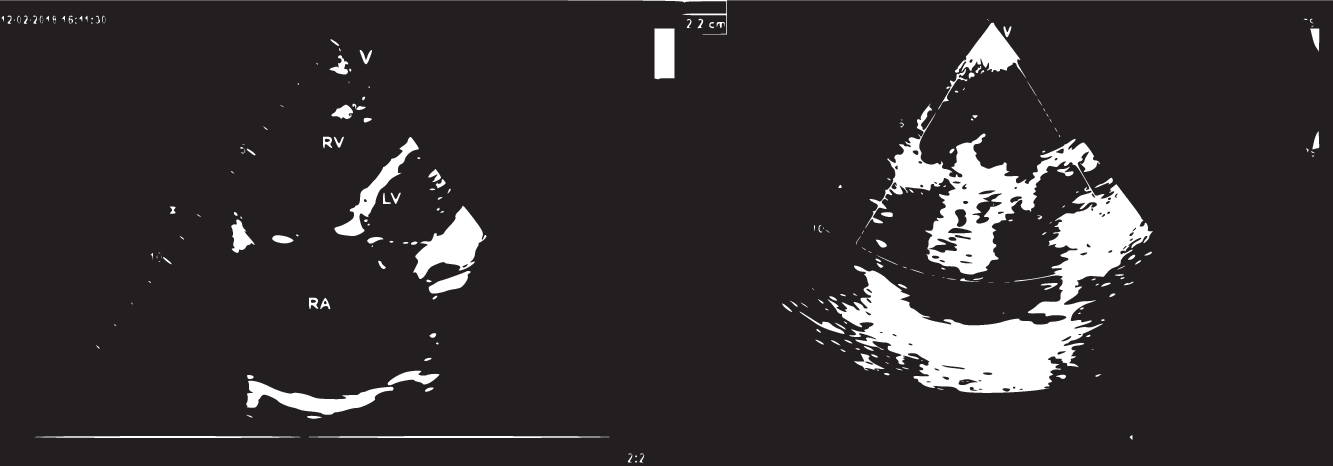

When the child aged 2 years and 10 months, he was symptomatic due to heart failure and presented to our clinic with tachycardia, tachypnoea, and hypotension. He was 11 kg (less than 3rd centile). On physical examination, liver was enlarged remarkably 4 cm below the costal margin. The gallop rhythm and diastolic murmur at left lower sternal edge were present. Cardiac enlargement was detected on chest radiography. Severe tricuspid and pulmonary regurgitation were detected on echocardiography. Tricuspid annulus measured 25 x 22 mm. Right atrium and right ventricle were dilated, and left ventricle was also diminutive (Fig 1). Cardiac MRI revealed right ventricular end-diastolic volume of 473 ml/m2 and right ventricular end-systolic volume of 352 ml/m2. The right ventricular ejection fraction was 25%, and the left ventricular ejection fraction was 46%. Left ventricular end-diastolic volume was 48 ml/m2 and end-systolic volume was 25 ml/m2.

Figure 1. Transthoracic echocardiography reveals severe right atrial dilatation and severe tricuspid regurgitation by colour Doppler.